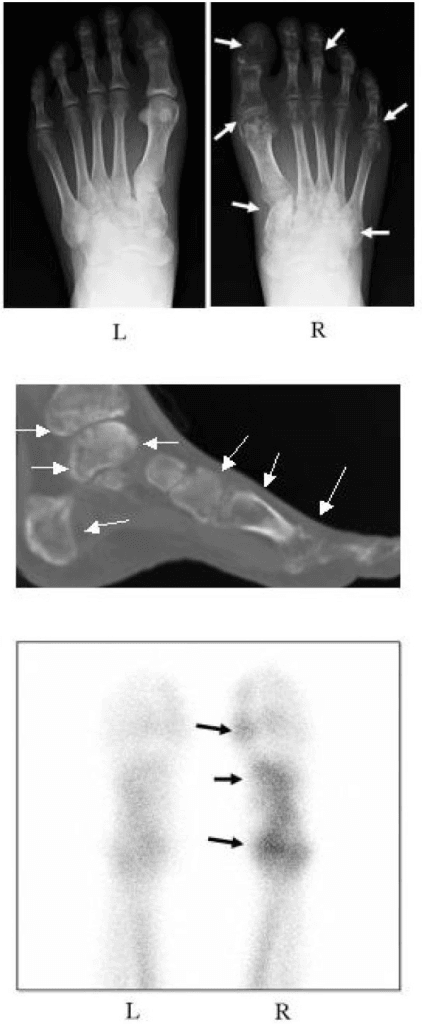

| 1. Global alignment | Is there valgus, varus, arch collapse, or rotational asymmetry? | Defines the deformity plane before drilling into joints |

| 2. Joint congruity | Do the ankle, subtalar, talonavicular, and TMT joints remain congruent under load? | Loaded incongruity can explain symptoms despite normal supine imaging |

| 3. Syndesmosis or midfoot interval | Is there diastasis or malreduction relative to the contralateral side? | High-yield indication for WBCT |

| 5. Bilateral comparison | Does the symptomatic side deviate meaningfully from the opposite side? | Reduces over-calling subtle anatomic variation |

- WBCT was most consistently useful for hindfoot alignment, syndesmotic assessment, and deformity analysis in the available literature.

- Loaded imaging frequently demonstrated greater deformity or instability than non-weight-bearing studies.

- WBCT produced reproducible 3D measurements of foot and hindfoot position in clinical use.

- The technique improved appreciation of loaded alignment beyond what is visible on supine CT.